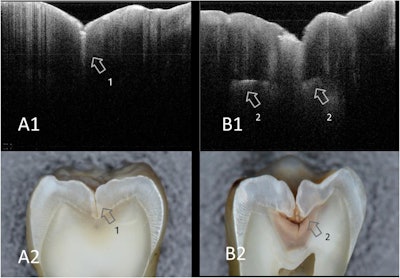

When this approach is used, sound enamel becomes nearly clear at the OCT wavelength range. It is easy to differentiate between enamel and dentin at the dentin-enamel junction because it looks like a dark border. Demineralized enamel and dentin show up as bright zones. This is due to the formation of many microporosities where the backscatter of imaging signals is increased, according to the authors.

Using SS-OCT, the upper margin of a cavity reflects the signal, appearing as a distinct bright border in cases of cavitated caries at the interproximal or occlusal hidden zone. This imaging approach can also determine the crack penetration depth of a tooth even when the fracture extends beyond the dentin-enamel junction, they wrote.